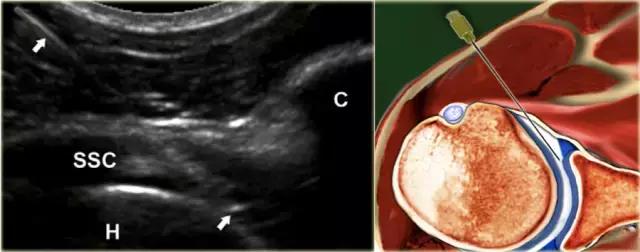

患者仰卧。腿被保持在微小的内旋和外展,从而缓和局部囊结构的紧张和使髂腰肌腱和囊在中心移出预期的针路径。优选地,使用5-3.5MHz的弯曲阵列换能器,其提供必要的穿透深度。通常,对于平均成年人使用长度为9cm的21号针。 在较小的成人或儿童中,可以使用23号5cm皮下注射针。

局部麻醉剂可以在主要注射之前注射,但是这需要额外的操作以及在关节中的非造影流体(麻醉剂)留下较少的空间,使有限的关节空间更小,以及可能的2个穿刺。

可以通过在包含麻醉剂和注射流体(对比剂或药物)的两个注射器之间使用三通连接器,来避免麻醉后换造影剂时引起的以外的脱针。